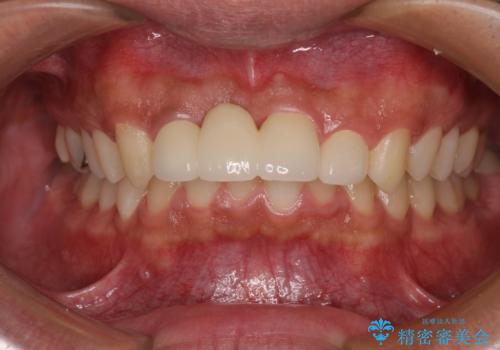

抜歯後の欠損部はブリッジにて補綴治療を行うこととしました。

事故直後のレントゲン写真では全ての歯の根尖部に骨透過像が認められましたが、治療後には全ての透過像がなくなっていました。

診断に2-3ヶ月かかりましたが、的確に診断を行うことができました。